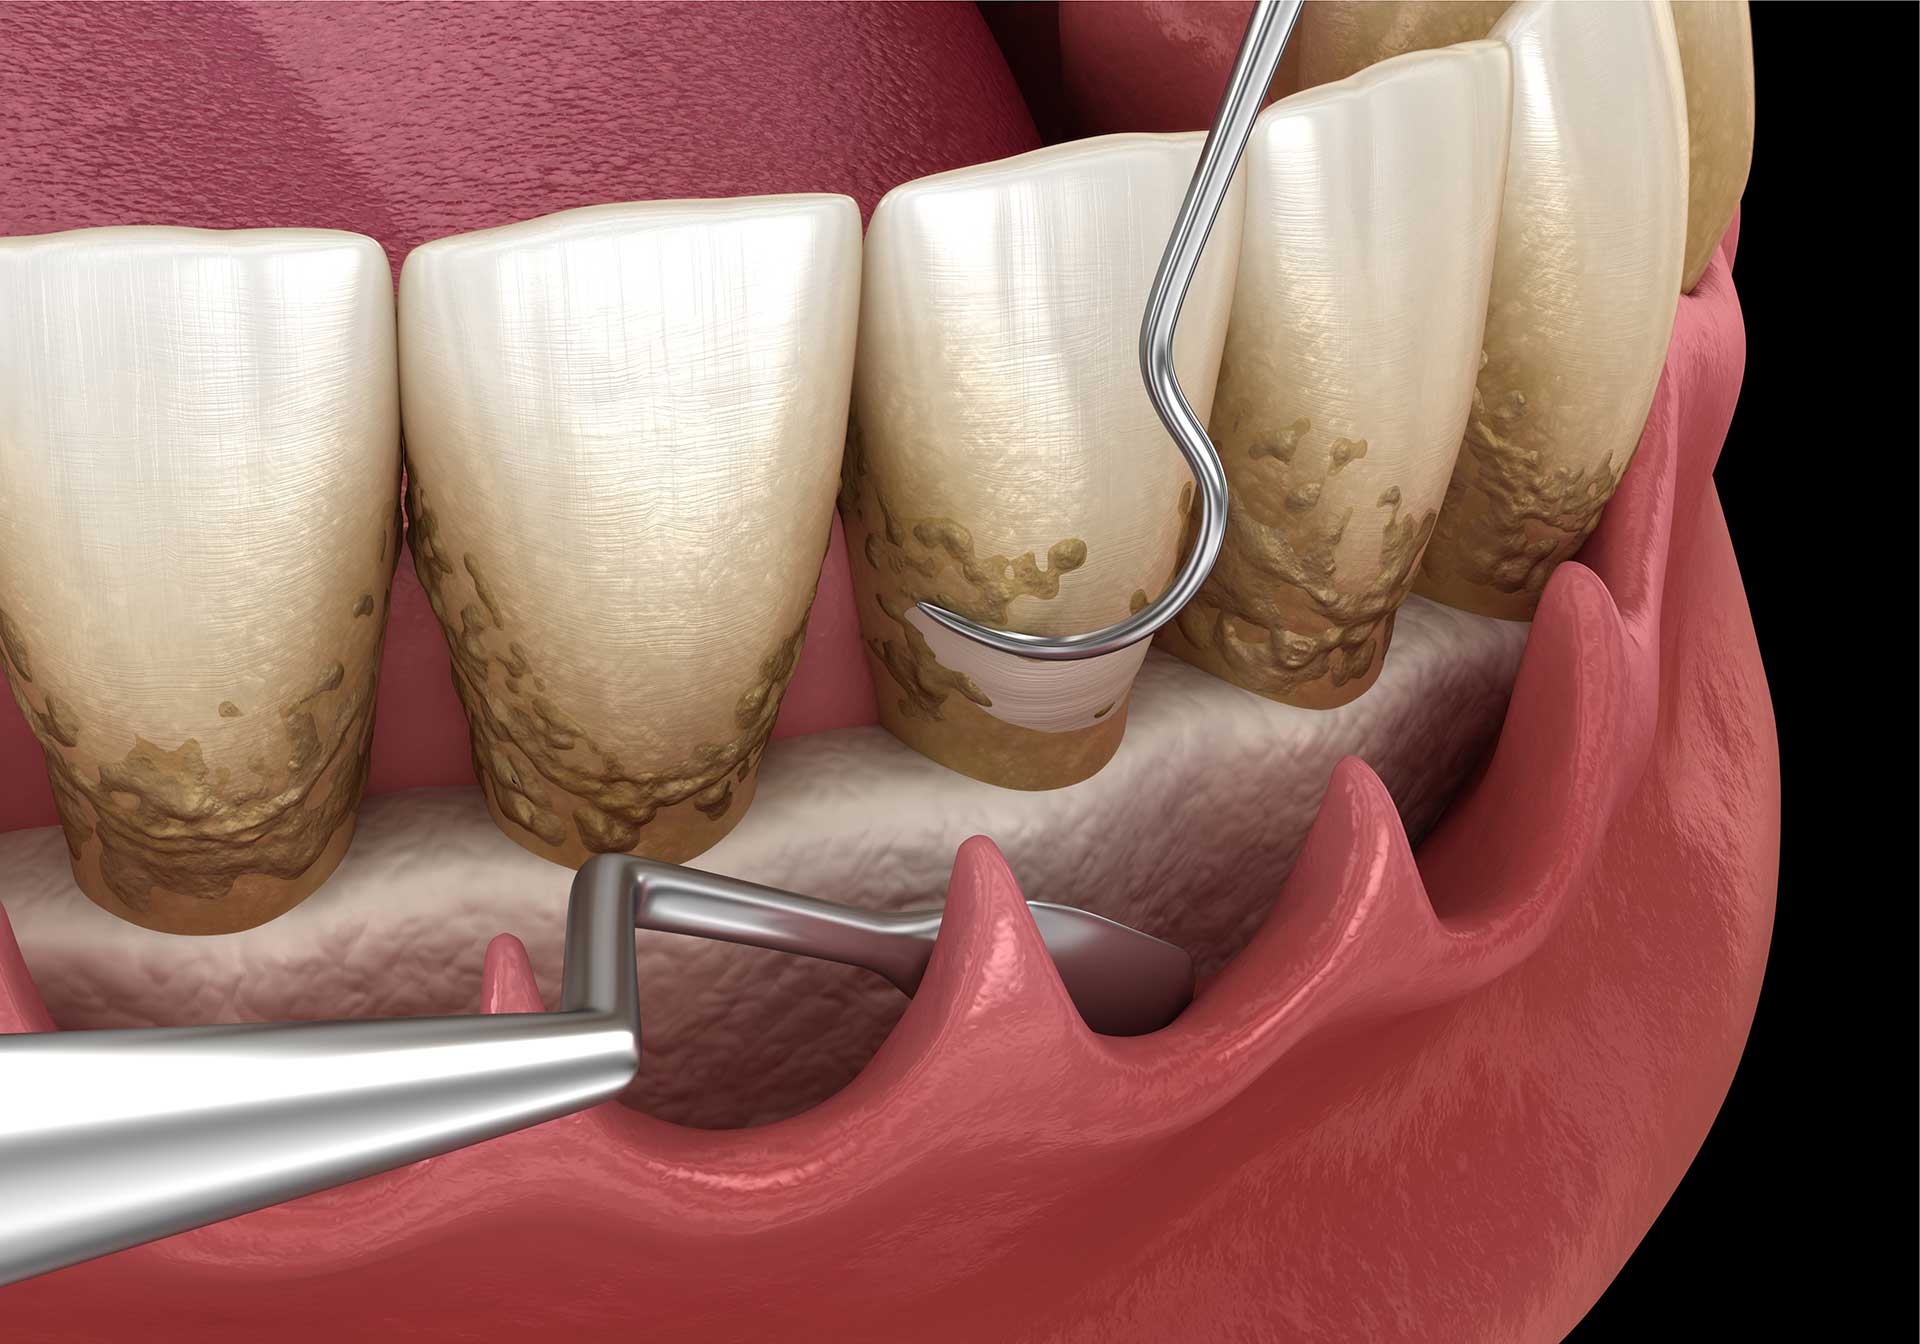

نحوه جرم گیری دندان در دندانپزشکی:

- جرم گیری و بروساژ دندان با ابزارهای دستی:

- جرم گیری با ابزار اولتراسونیک:

طبق یک مقاله علمی در حوزه دندانپزشکی مدرن عنوان “اثربخشی ابزار آلتراسونیک در مقابل ابزارهای دستی” ابزار نوین دندانپزشکی در جرمگیری دندان یا به عبارتی جرمگیری به روش جدید کارایی و تاثیری بیشتری خواهد داشت؛ این مقاله در یک مرور سیستماتیک بر جرم گیری دندان عنوان میکند، ابزارهای جرم گیری اولتراسونیک را در مقایسه با ابزارهای سنتی دستی در روش های نوین جرم گیری دندان کارایی و اثر بخشی بیشتری داشته و عواملی مانند نتایج بالینی، راحتی بیمار و زمان کوتاه تر درمان، و نظر متخصصان دندانپزشکی مهر تائیدی بر ارزشمندی و کارایی مثبت این ابزار نوین جرمگیری دندان است.